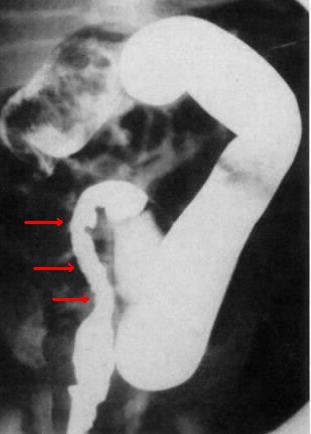

Aspect

radiologique d'une megacolon congenitale (

Hirschprung disease ) . Image de la portion

aganglionaire est tres net sur le cliche OPG (

fleche rouge ) . Sa lumiere est peut serre , lisse ,

mou ( fleche rouge ) . La colon en amont est dilate

, perdre des hautres et la portion en aval est

presque normale . |

Megacolon congenitale

( maladie de Hirschprung ) La colon en amont est

dilate et la portion aganglionaire ( fleche rouge )

est aperitaltisme et serre . La colon rectale en

aval est normale . Lavement baryte du colon , cliche

de face . |

La portion non

innerve du colon

se propulse le bol fecale vers en amont et

la colon se distend . Aspect radiologique lavement

baryte du colon sigmoide . |